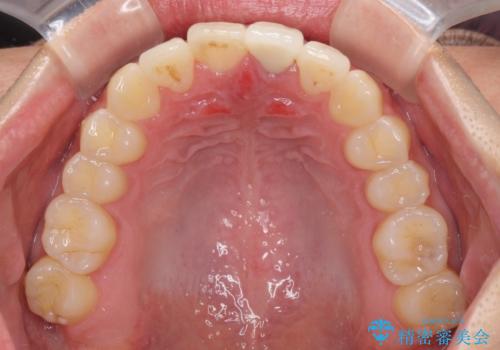

前歯の歯並びとクラウンを改善 インビザラインとオールセラミック

上下前歯の歯列不正はインビザラインにより歯列を整え、その後に、前歯をオーダーメイドタイプのオールセラミッククラウンにて補綴治療することとしました。

初診時には、歯並びを整えることのみを検討されていましたが、歯列が整うにつれて不自然な色合いが気になるようになり、矯正治療を行ってから補綴治療をする計画を受け入れてくださいました。

口元の印象が明るく変わり、患者様には大変満足していただきました。